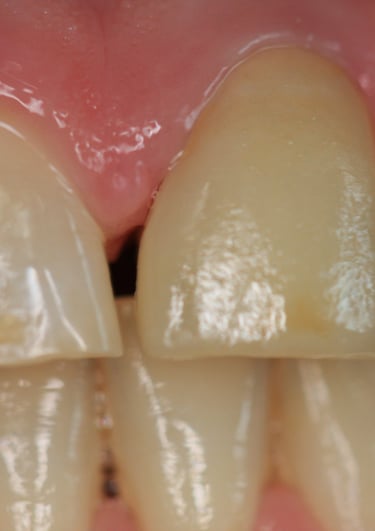

Corona incongrua: non solo non si armonizzava con i denti circostanti, ma risultava anche inadeguata dal punto di vista funzionale.

Corona Incongrua

Condizioni Iniziali

Moncone non ritentivo